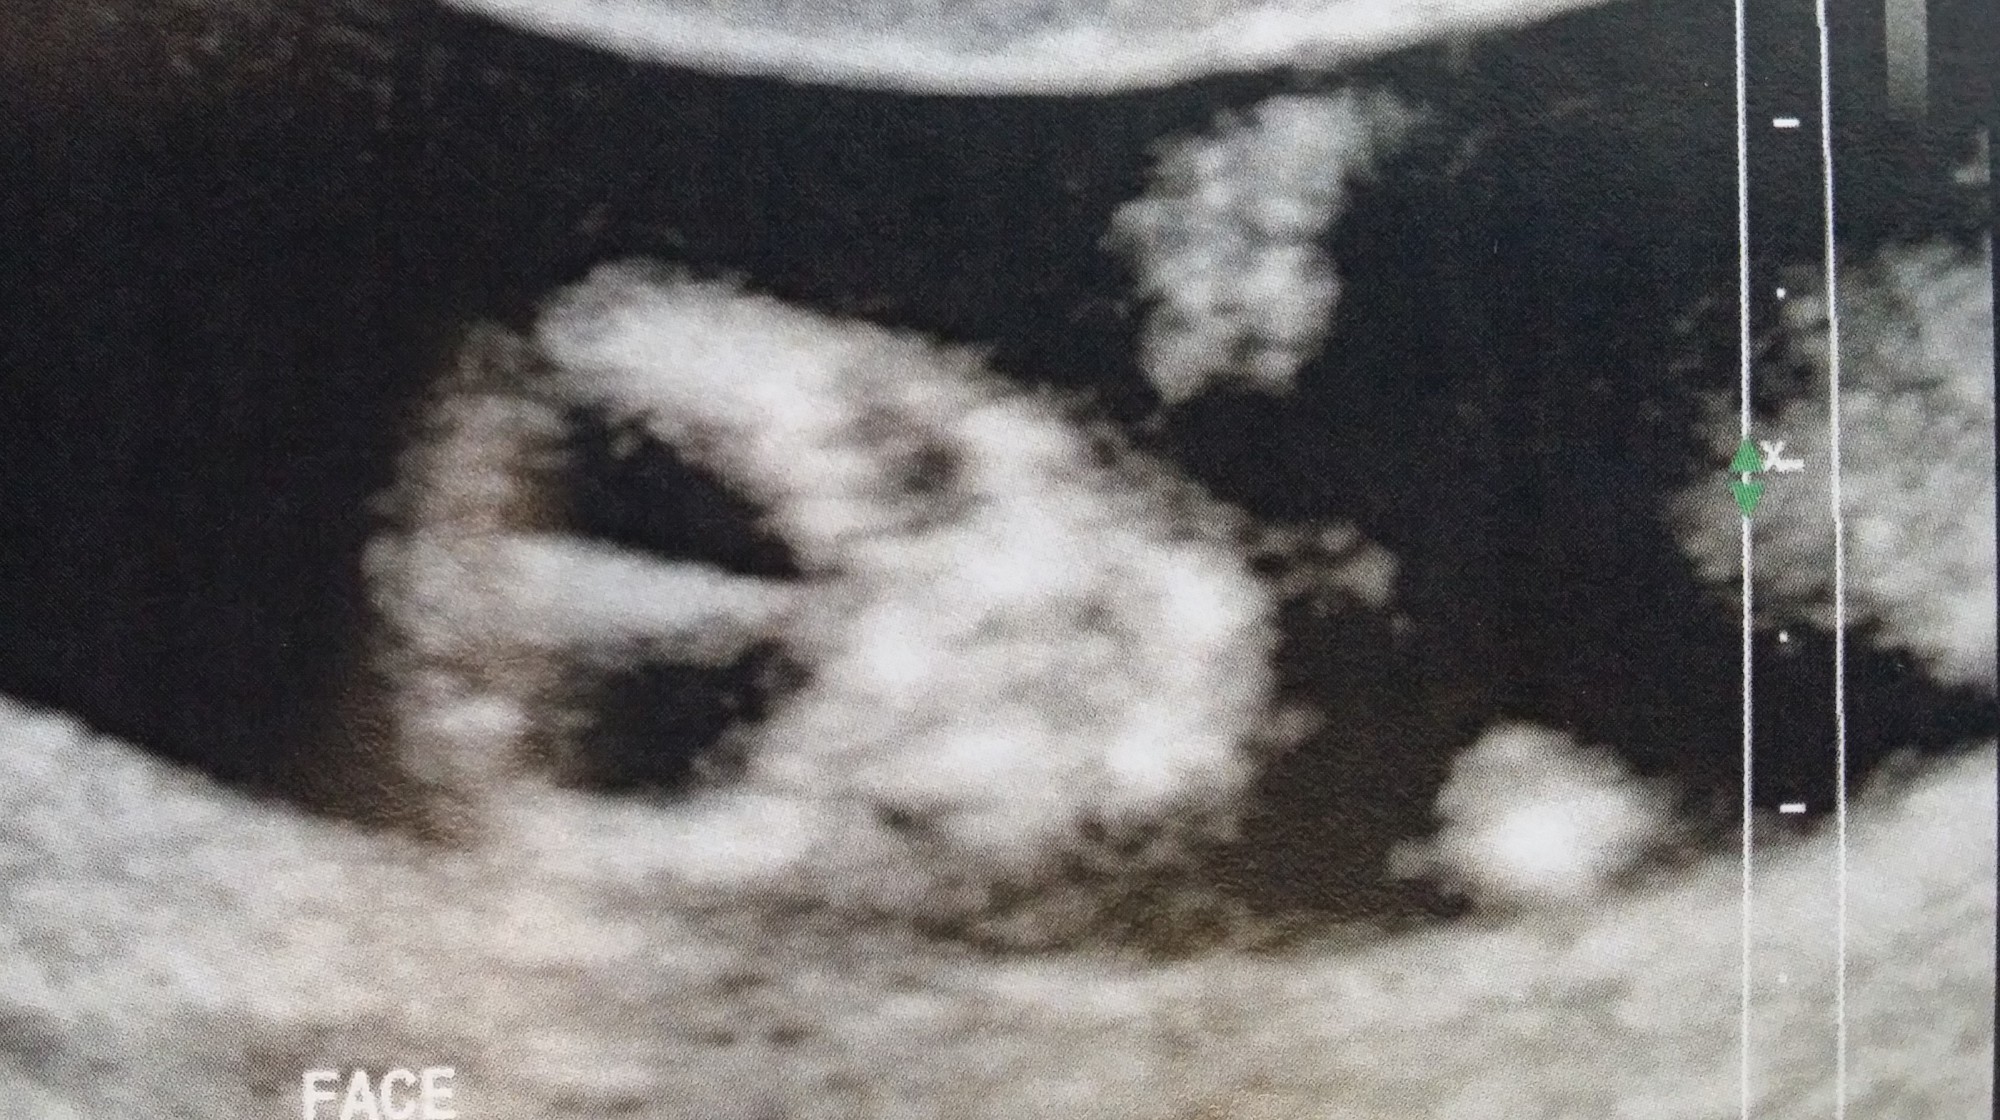

The ‘Screenage’ header image is from the next scan. It was one of my favourite cause it looks like it’s giving a little fist pump which is what I was doing while watching it. This time around I feel much more in touch with reality which I actually prefer in a way. Things are looking good. She’s 26 weeks, bloated and there’s definitely a little human (or limbed alien) moving around in there! – Why is it that we keep thinking of it as an alien – is it because of the movie franchise? My partner thinks so.